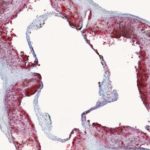

Il grasso addominale, più di qualsiasi altro tipo di grasso corporeo, aumenta il rischio di insulino-resistenza e diabete di tipo 2. I ricercatori sanno che il grasso addominale diventa pericoloso quando diventa infiammato, ma hanno avuto difficoltà a determinare che cosa causa l’infiammazione.

Un nuovo studio della Columbia University Irving Medical Center (CUIMC) ha rivelato che almeno uno dei responsabili di questa misteriosa infiammazione proviene dal fegato. I ricercatori hanno scoperto che, nei topi obesi, il fegato aumenta la produzione di un enzima chiamato DPP4. Questo enzima viaggia attraverso il flusso sanguigno verso il grasso addominale. Una volta all’interno del tessuto grasso, DPP4 aiuta ad attivare le  infiammatorie.